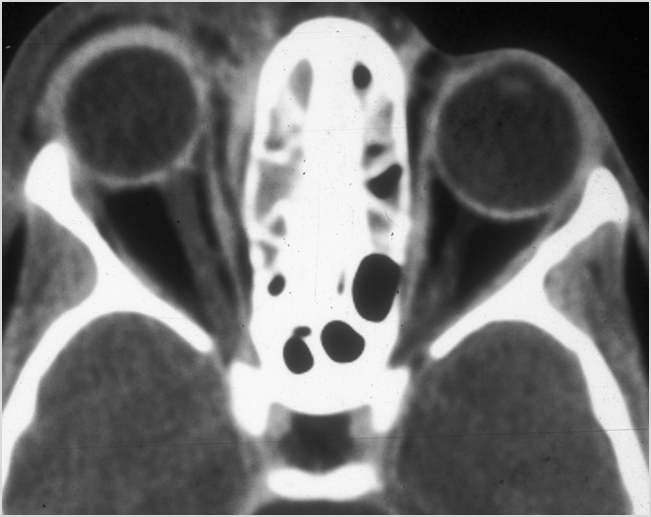

Orbits

The extraconal orbital fat is abnormal.

There is a subperiosteal abscess or edema along the medial wall, roof or floor of the orbit.

The extraocular muscles are swollen or otherwise abnormal.

There is bone erosion along the walls of the orbit.

The superior and/or inferior ophthalmic veins are dilated or thrombosed.

Eyes

Proptosis is present.

The optic nerve is stretched in appearance.

Signs of tension orbit or endophthalmitis are present.